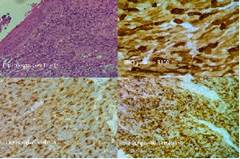

Se realiza estudio histológico con técnica de inmunohistoquímica (IHQ) que informa: neoplasia maligna sólida, fusocelular y epitelioide, positiva para S100, Melan-A y HMB -45, lo que confirma el diagnóstico de melanoma anal (Figura 2).

Figura 2 Estudio histológico con inmunohistoquímica que informa neoplasia maligna sólida, fusocelular y epitelioide positiva para S100, Melan-A y HMB -45.

Un minucioso examen proctológico, junto con la anoscopía y la búsqueda de adenopatías son fundamentales para determinar las características de la lesión, permitiendo excluir los diagnósticos diferenciales más frecuentes. El diagnóstico de MA se realiza mediante biopsia y tinción IHQ. Los melanocitos pueden presentarse de varias formas: pleomórficos, epitelioides, células fusiformes, entre otras, dificultando el diagnóstico diferencial con otros tumores como sarcomas, tumores gastrointestinales (GIST) y carcinomas indiferenciados. El diagnóstico es posible gracias a la tinción IHQ para proteínas S-100, HMB-45, Melanina A y Mart-14)(9.